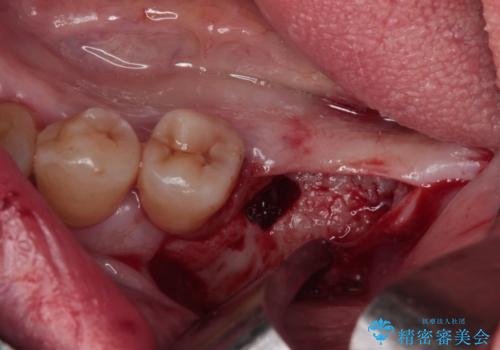

全体的に歯肉が腫れており、歯周病により抜歯をしなければならない歯がある状態でした。

矯正治療を仕上げ、必要に応じて歯周外科処置を行い、適宜インプラントを埋入しながら咬み合わせを回復させていくこととしました。

最終的に奥歯はオールセラミッククラウンによる補綴治療を行うこととしました。

治療前は磨き残しが多く見られ、全体的に歯肉が腫れている状態でしたが、抜歯の必要な歯を抜いたことで口腔内の環境が改善され、磨き残しも少なくなってきました。